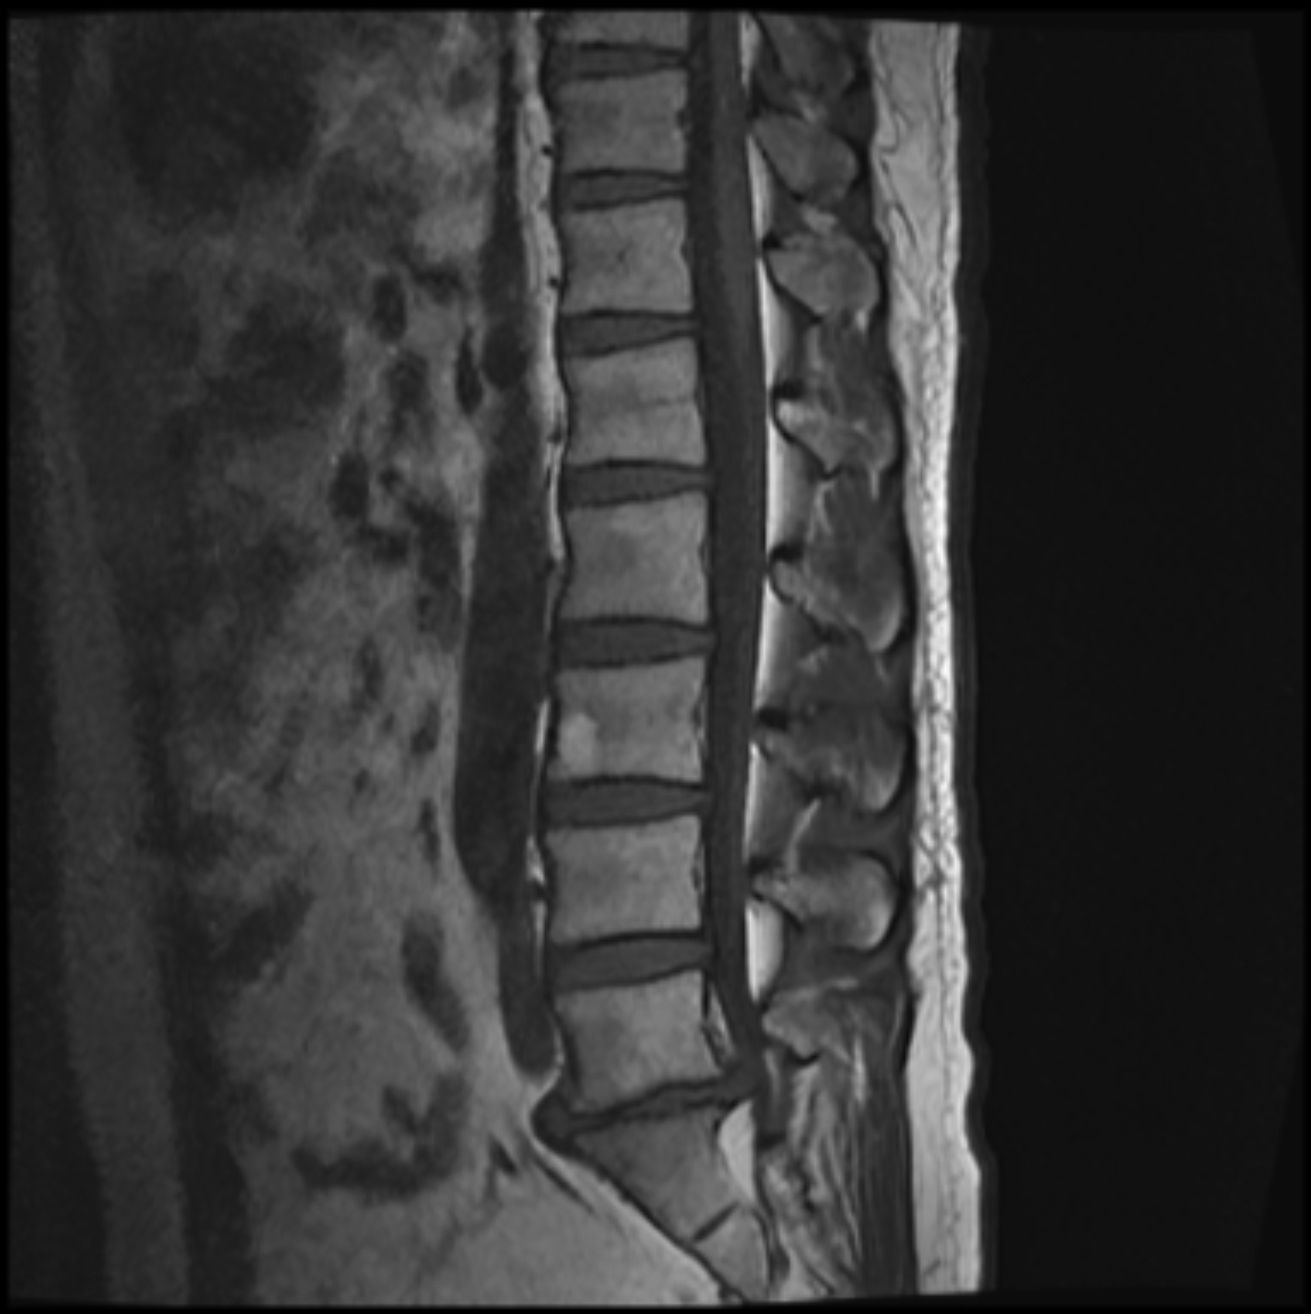

MR报告

放射学表现

腰椎生理曲度变直 , 椎体排列尚整齐 ; 腰3椎体偏前侧见 0.9x 1.4cm的椭圆形较高信号灶 , 压脂后信号减低 , 余所示 椎体信号未见明显异常 , 各椎体边缘骨质增生改变 , 骨性 椎管未见明显狭窄 ; 腰5/聶1椎间隙变窄 , 相对缘终板面略 毛糙 , T2WI/FS信号稍高 ; 腰5/髓1椎间盘向后明显突出 致局部椎管变窄 , 马尾终丝受压 ; 腰3/4、4/5水平椎间盘 向周围轻度膨隆 , 硬膜囊略受压 ; 余圆锥、马尾形态、信 号未见明显异常。

放射学诊断

1.腰5/艇1椎间盘明显突出 , 致局部椎管变窄。 2.腰3/4、 4/5椎间盘轻度膨隆。 3.腰3椎体异常信号灶 , 考虑脂肪沉 积可能 , 请随诊。 4.腰椎轻度退变 , 生理曲度变直 ; 腰5/ 融1椎体相对缘终板炎改变。